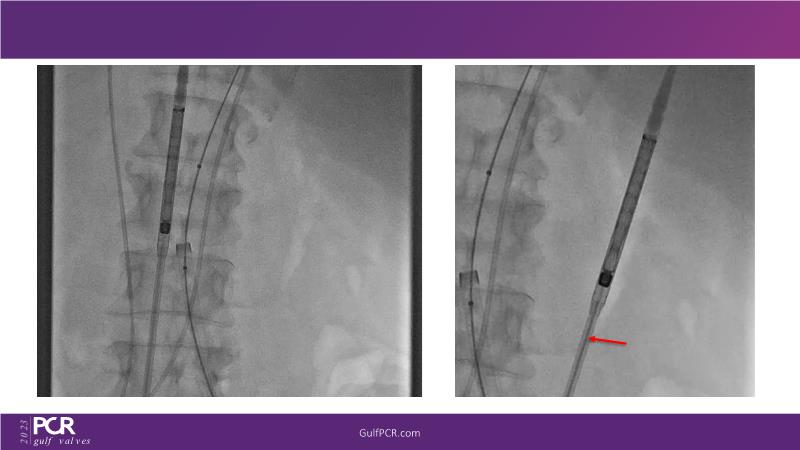

The primary focus of this GulfPCR-GIM 2023 session revolves around pre-procedural planning considerations, valve selection, and managing complex anatomies using both traditional self-expanding valves and the Evolut FX system. Additionally, the session aims to explore the work-up protocol for patients grappling with severe AS and advanced CKD, elucidate the algorithm for selecting the appropriate TAVR platform, discuss strategies to reduce contrast utilization, and highlight the distinctive advantages offered by the Evolut FX system.

• To learn more about optimization of valve deployment